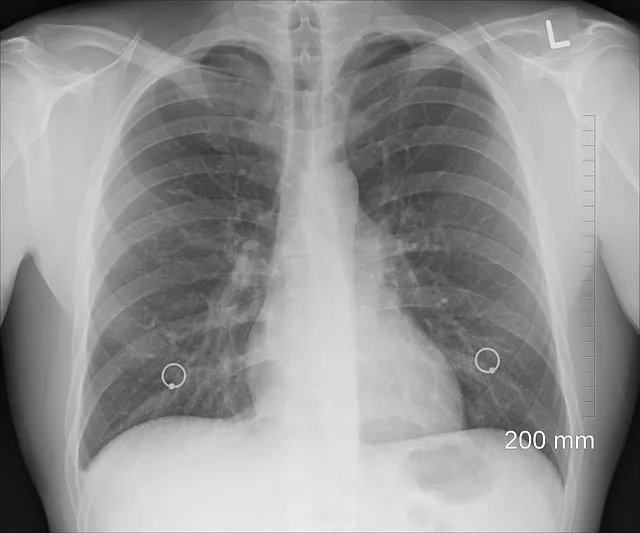

만성 폐쇄성 폐질환은 흡연, 환경 오염, 미세 입자, 유전적 요소와 관련된 폐 기능의 지속적인 감소를 특징으로 하는 질환입니다. 이 질환은 주로 만성 기침, 가래, 호흡 곤란과 같은 증상으로 나타나며, 이로 인해 환자의 삶의 질이 저하될 수 있습니다.

만성 폐쇄성 폐질환는 폐렴, 폐색전증, 폐쇄성 기종성 질환 등 다양한 형태로 나뉠 수 있습니다. 이러한 질환은 조기 발견과 관리가 중요하며, 효과적인 치료와 건강한 생활습관을 통해 예방할 수 있습니다.